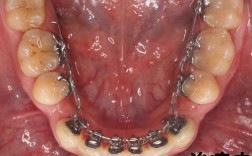

- 托槽脱落/松动: 强大的磨牙力容易导致粘在牙齿上的托槽(小铁片)脱落或松动。

- 弓丝变形/断裂: 磨牙力可能使连接托槽的弓丝变形、弯曲甚至断裂,使矫正系统失效。

- 其他附件损坏: 舌侧扣、橡皮筋牵引钩等附件也可能受损。

- 正畸医生会根据你的情况调整矫正方案,可能选择更坚固的托槽和弓丝,并增加复诊频率检查磨牙对矫正器的影响。